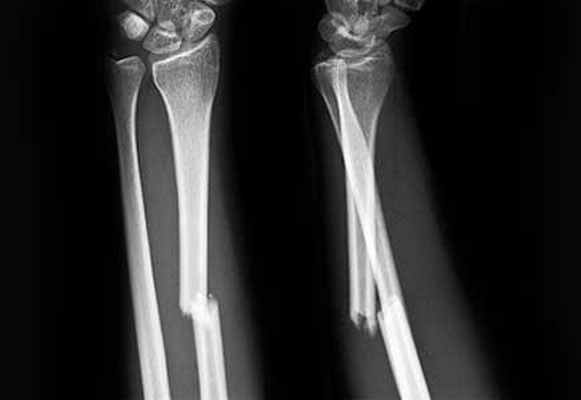

Переломы костей предплечья могут быть изолированными, а могут и сочетаться с другими повреждениями. Переломы костей предплечья чаще встречаются со смещением отломков, реже без смещения. В зависимости от уровня перелома различают — повреждение проксимального отдела, повреждение диафиза, повреждение дистального отдела предплечья. Переломы костей предплечья могут быт закрытыми — встречаются чаще, и открытыми — более реже.

При диафизарном переломе локтевой и лучевой кости, не осложненной смещением, предплечье фиксируют в положении сгиба с захватом лучезапястного и локтевого суставов сроком на пять недель. При переломе со смещением выполняют репозицию (восстановление правильного положения смещенных отломков кости) и накладывают гипсовую повязку сроком до шести недель.

При диафизарном переломе обеих костей предплечья без смещения на руку, согнутую в локте, накладывают лонгет, захватывая лучезапястный и локтевой сустав сроком до восьми недель. При смещении отломков проводят репозицию или остеосинтез в зависимости от тяжести повреждения. После оперативного вмешательства накладывают гипсовую повязку сроком до трех месяцев.

Переломы диафизарного отдела костей предплечья